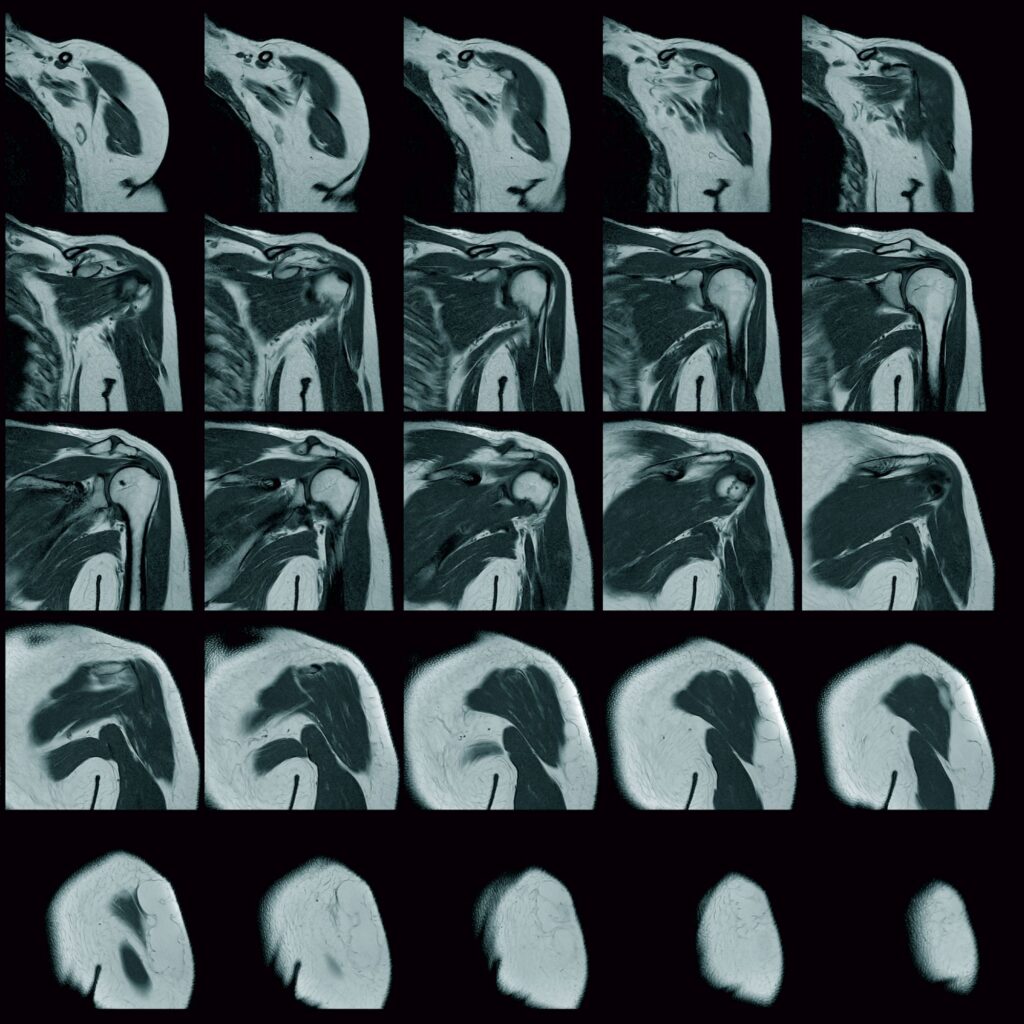

Η αξονική τομογραφία (CT) δίνει καλές πληροφορίες που αφορούν τις οστικές δομές, αλλά υπάρχουν περιορισμοί όσο αναφορά τους μαλακούς ιστούς. Η μαγνητική τομογραφία (MRI) είναι η εξέταση εκλογής και αναδεικνύει τις μορφολογικές μεταβολές που συμβαίνουν στου μεσοσπονδύλιους δίσκους, το νωτιαίο μυελό, τις νευρικές ρίζες και του γύρω μαλακούς ιστούς. Η διάγνωση δεν θα πρέπει να στηρίζεται μόνο στα ακτινολογικά ευρήματα καθώς σε μελέτες έχει φανεί ότι ένα υψηλό ποσοστό ανθρώπων με ευρήματα από τη μαγνητική τομογραφία (περίπου 30%) είναι ασυμπτωματικοί. Όταν τα κλινικά ευρήματα ταιριάζουν με τα ακτινολογικά, τότε αυξάνονται τα ποσοστά σωστής διάγνωσης. (6,12,13)